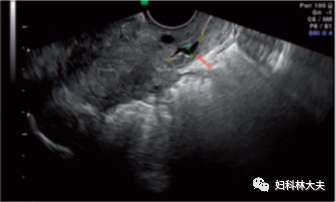

曾经看到一篇文章讲:没有发生疤痕憩室的患者,疤痕与宫颈内口的中位距离为 4.6 mm(0-19 mm),而有疤痕憩室的患者疤痕与宫颈内口的中位距离为 0(0-26 mm),89% 的憩室位于疤痕中央,其余位于疤痕两侧。

这个也给我们一个提示:宫颈解剖内口就是一个界标,越靠近宫颈解剖内口做切口越容易发生疤痕憩室,可事实上在做剖宫产的时候这个界标是很难找到的,靠手触摸感觉肌层的厚度分界终究不靠谱。